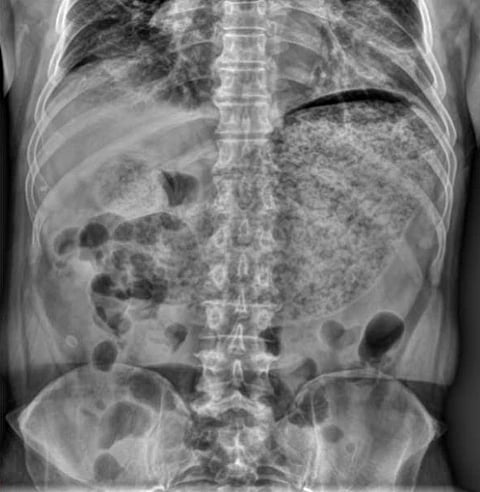

Plain abdominal X-ray reveals a large amount of material in the stomach, suggesting severe gastric hypomotility.

Gastroparesis occurs when the stomach cannot move food into the small intestine at a normal pace. In diabetes, repeated fluctuations in blood glucose can damage the vagus nerve, which controls stomach muscle contractions.Dong Seok Lee1 and Sang Jin Lee/Wikimedia Commons